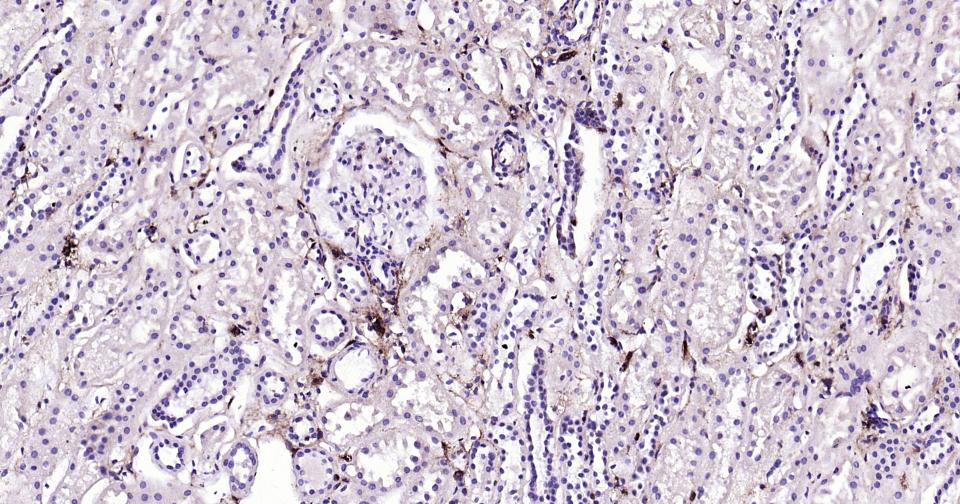

| IHC-P | Human | 1:100-500 | |